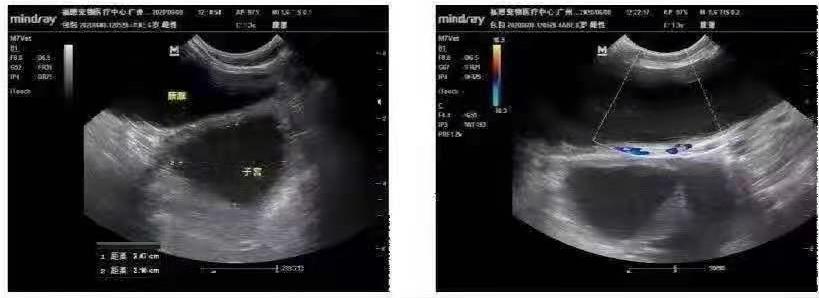

大龄犬b超检查

两侧子宫角扩张

可见无回声液性暗区

内壁粗糙

左右两侧卵巢扫查未见